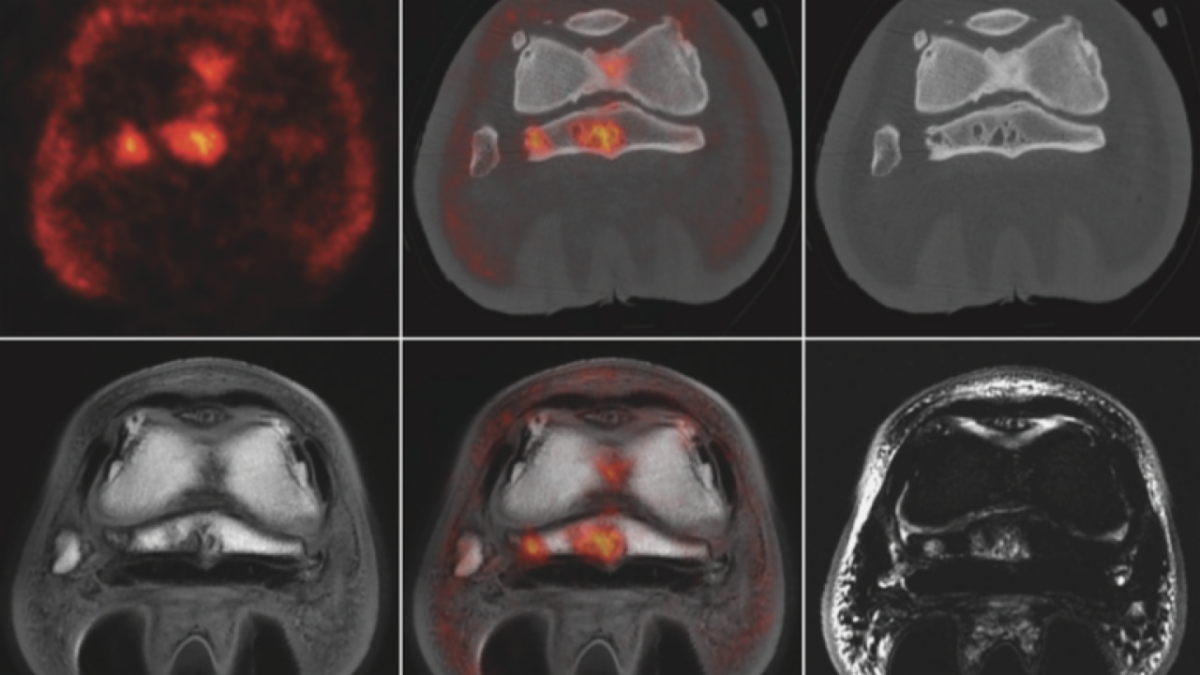

Advances in Diagnostic Imaging Improve How Radiologists “See” Horses’ Legs

Scientific journals Veterinary Radiology & Ultrasound, Equine Veterinary Education, and the Equine Veterinary Journal are celebrating the publication of nearly 100 equine imaging papers in the last five years. In particular, the evolution of computed tomography (CT), the introduction of positron emission tomography (PET), and the continued growth of magnetic resonance imaging (MRI) have transformed how we image horses’ legs and have led to important clinical advances. UC Davis radiology professor Dr. Mathieu Spriet, who pioneered the use of PET in horses, was one of the guest editors for this special issue.